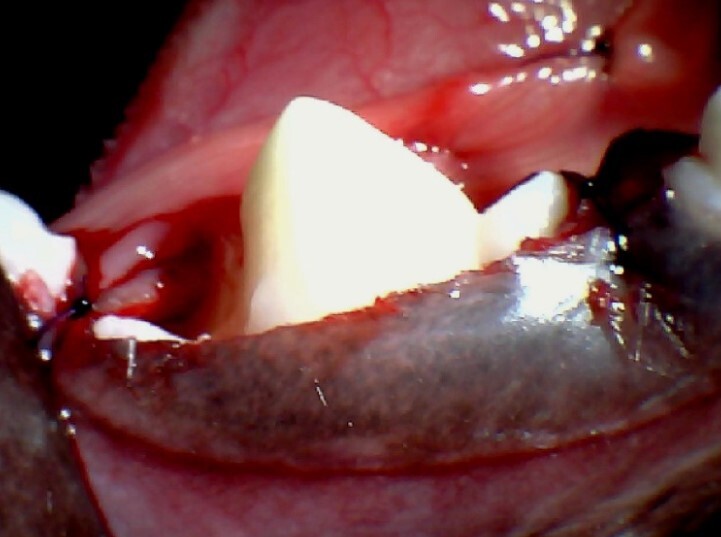

사진에서 보이는 것과 같이 아래턱에서 가장 큰

어금니가 잇몸에 덮여 맹출 되지 못하고 있는 것이

확인됩니다.